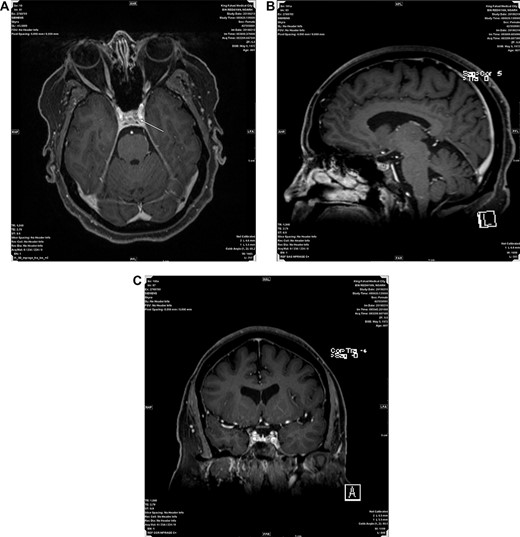

(A, B and C) Represent post contrast Axial, Sagital and Coronal MRI images respectively, showing a small non enhancing nodule in left side of adenohypophysis measuring 5.5 mm suggestive of microadenoma.

A 47 years old female known case of type 2 diabetes mellitus and Hypertension presented with muscle weakness and gain weight. On physical examination, the patient had large, rounded face (moon face), increased fat in her neck and shoulder areas (buffalo hump) and with thinner arms and legs (central obesity). Her laboratory investigations showed high cortisol level (489 nmol/L) with normal Adrenocorticotropic hormone (ACTH) plasma level (11.1 pmol/L). MRI scans showed a 5 mm solid mass in left side pituitary gland. Figure 1A–C representing post contrast axial, sagittal and coronal images, respectively, showed a small non-enhancing nodule in left side of adenohypophysis of the pituitary gland measuring ~5.5 mm. Imaging features suggested microadenoma. The patient underwent transsphenoidal pituitary tumor resection. The histopathological findings were of H&E stained sections showing multiple fragments of tumor tissue exhibiting elongated and bipolar spindle cells arranged in a fascicular and storiform patterns with adjacent unremarkable pituitary gland. The individual tumor cells contained slightly fibrillary eosinophilic cytoplasm with oval nuclei (Fig. 2A and B). A panel of IHC studies was done, which revealed that the spindle neoplastic cells are positive for thyroid transcription factor-1 (TTF-1) (diffuse nuclear staining), S100 and glial fibrillary acidic protein (GFAP) (rare cells) (Fig. 3A and B). These findings are consistent with a pituicytoma.